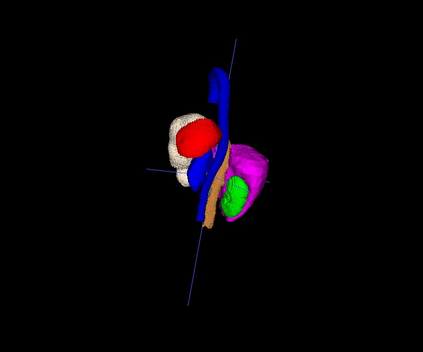

Interactive segmentation, an integration of AI algorithms and human expertise, premises to improve the accuracy and efficiency of curating large-scale, detailed-annotated datasets in healthcare. Human experts revise the annotations predicted by AI, and in turn, AI improves its predictions by learning from these revised annotations. This interactive process continues to enhance the quality of annotations until no major revision is needed from experts. The key challenge is how to leverage AI predicted and expert revised annotations to iteratively improve the AI. Two problems arise: (1) The risk of catastrophic forgetting--the AI tends to forget the previously learned classes if it is only retrained using the expert revised classes. (2) Computational inefficiency when retraining the AI using both AI predicted and expert revised annotations; moreover, given the dominant AI predicted annotations in the dataset, the contribution of newly revised annotations--often account for a very small fraction--to the AI training remains marginal. This paper proposes Continual Tuning to address the problems from two perspectives: network design and data reuse. Firstly, we design a shared network for all classes followed by class-specific networks dedicated to individual classes. To mitigate forgetting, we freeze the shared network for previously learned classes and only update the class-specific network for revised classes. Secondly, we reuse a small fraction of data with previous annotations to avoid over-computing. The selection of such data relies on the importance estimate of each data. The importance score is computed by combining the uncertainty and consistency of AI predictions. Our experiments demonstrate that Continual Tuning achieves a speed 16x greater than repeatedly training AI from scratch without compromising the performance.